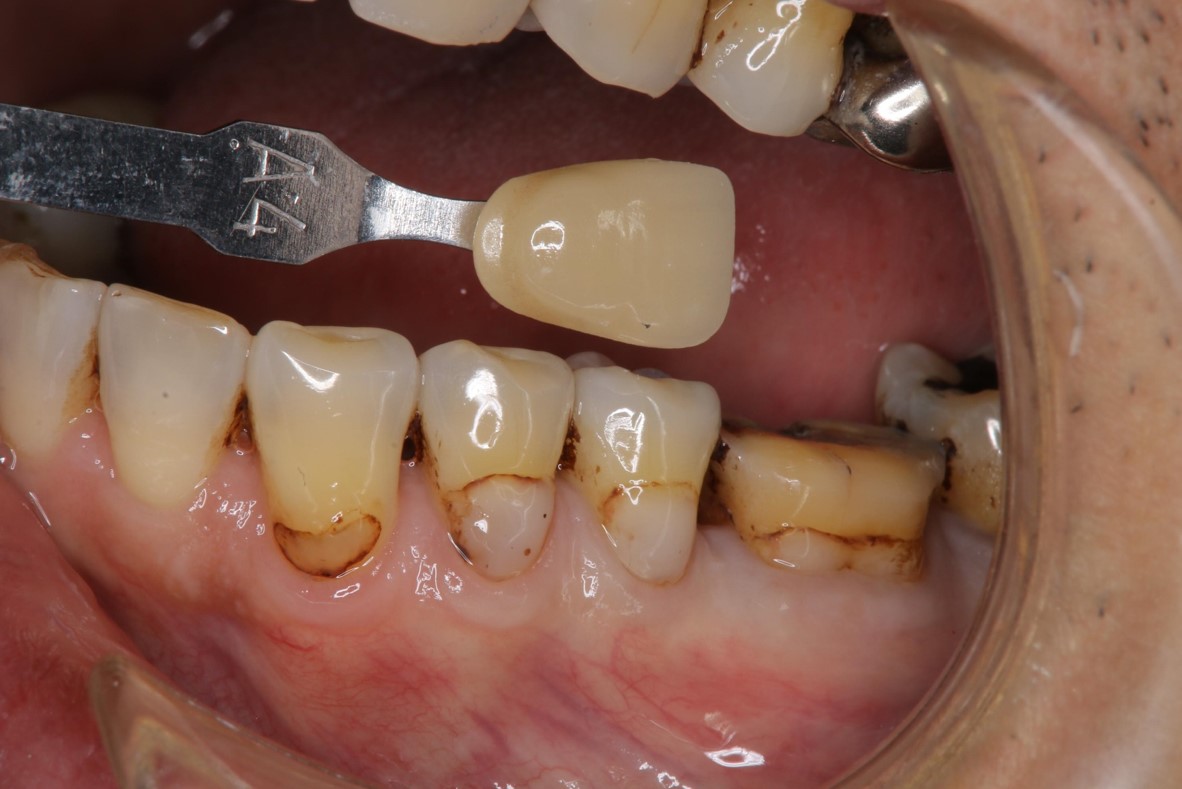

陶瓷冠塊體製備

照相比色